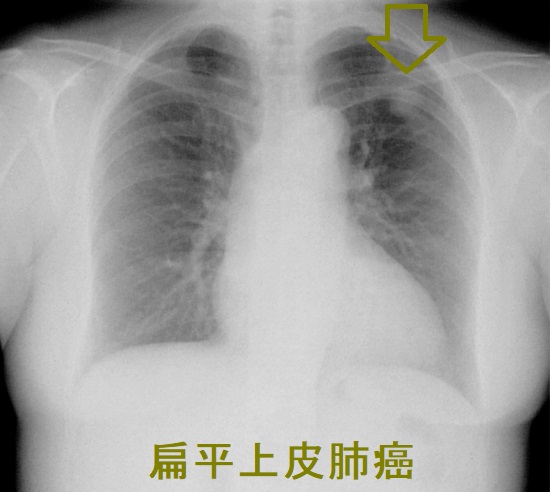

扁平上皮癌(末梢肺癌)

扁平上皮肺癌(末梢肺癌) 胸部エックス線写真

扁平上皮肺癌(末梢肺癌) 胸部エックス線写真;左上葉に辺縁不整な腫瘤陰影